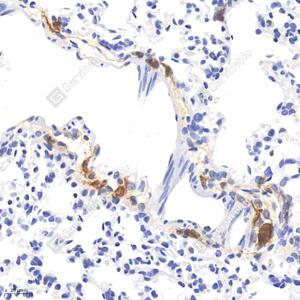

IHC检测CD163蛋白(货号 GB113751). 样品: 小鼠肺, 4%多聚甲醛 (货号G1101) 固定12-24小时. 抗原修复: 柠檬酸抗原修复液(干粉, pH 6.0) (G1201), 98℃, 20分钟. —抗: 1: 500稀释, 4℃ 孵育过夜. 二抗: HRP标记山羊抗兔IgG (H+L) (货号GB23303), 1: 200稀释, 室温孵育1小时. |